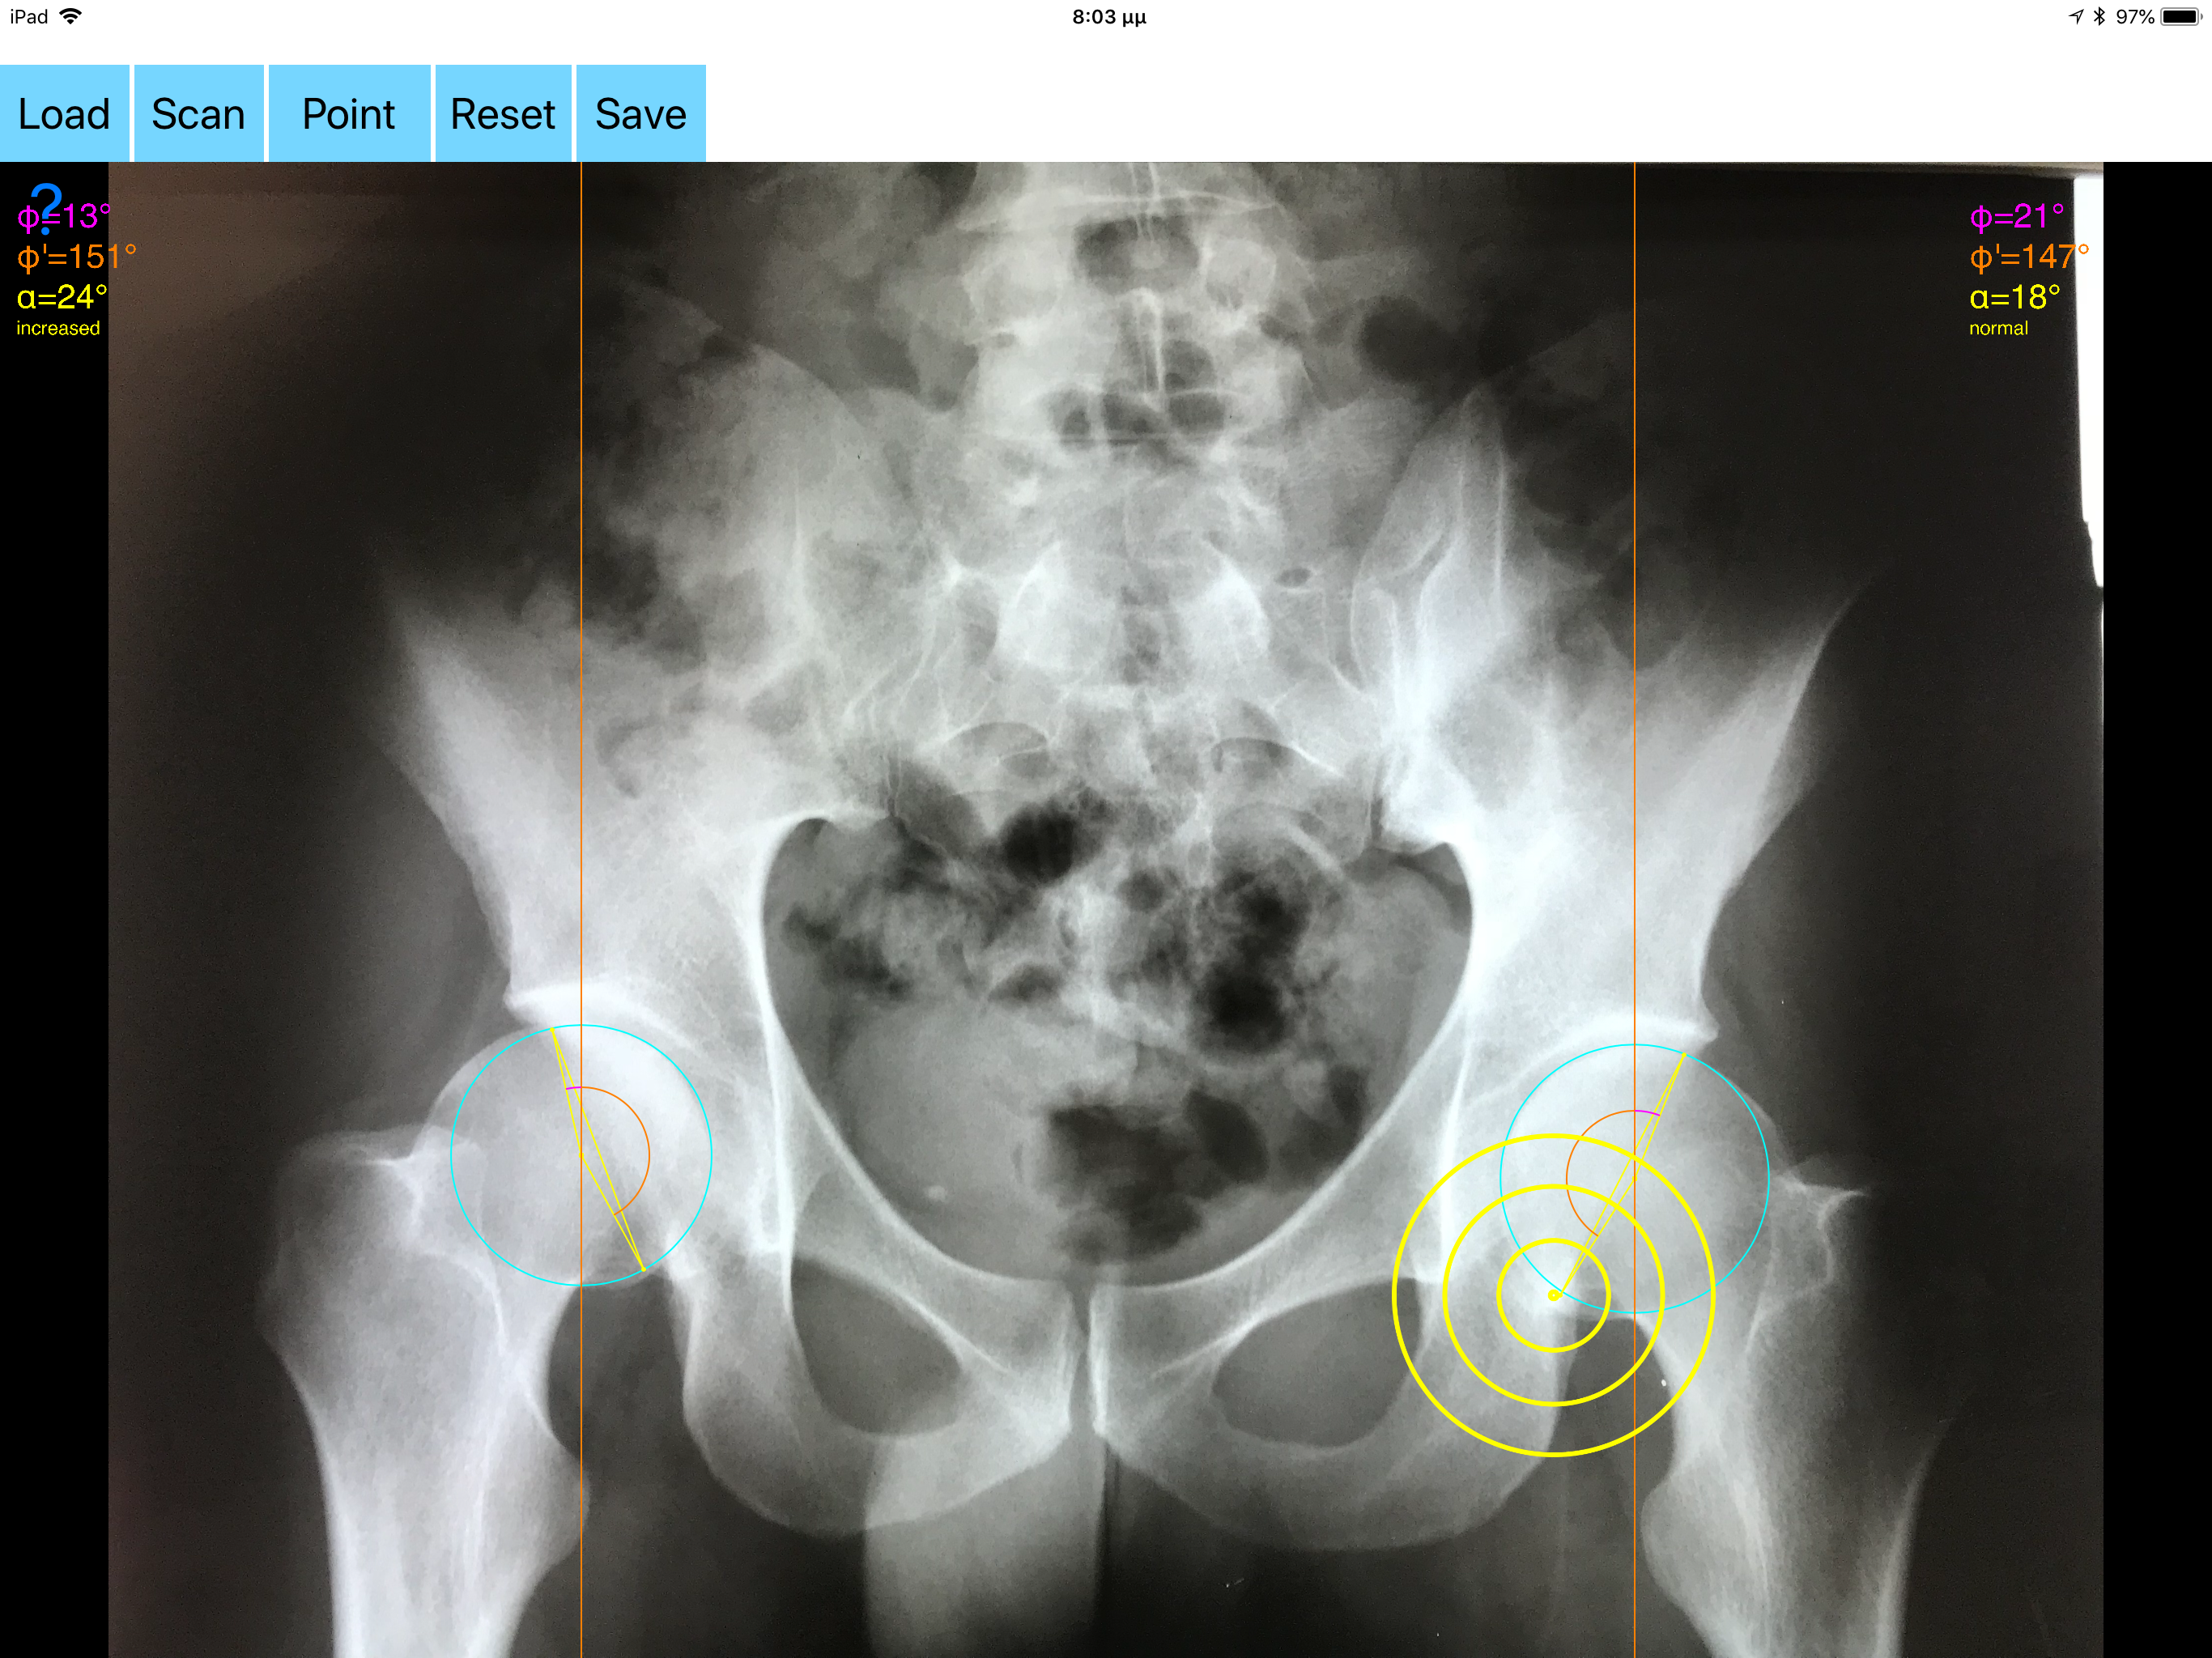

Acetabular version refers to the anteroposterior orientation of the acetabular opening relative to the true horizontal axis of the pelvis. The normal human acetabulum is anteverted in order to allow impingement free range of motion including flexion, adduction, and internal rotation. Abnormal acetabular version has been correlated with pathologic hip conditions including femoroacetabular impingement (FAI) and developmental hip dysplasia.The association between acetabular version and hip pain has been well established in recent years as a source of contributing to early hip osteoarthrosis and labral tears. Recognition and appropriate treatment of abnormal acetabular version is crucial to preventing irreversible damage to the hip Acetabular version is conventionally evaluated on CT scans but excessive radiation doses associated with routine use of computed tomography (CT). An objective radiographic tool which provides measurements comparable in accuracy to CT measurements has been developed by Dr. Hefti (Nomogram).Tedious and time-consuming calculation has to be done in simple X-rays in order to calculate the acetabular anteversion. The primary goal of this App is to help determine radiographic values of acetabular anteversion in a practice in a blink of an eye and avoiding CT scans. The App is medical software aimed for orthopaedic surgeons, providing tools that allow doctors to: -Securely import medical images directly from the camera or stored photos. -By marking certain points in a simple standard AP pelvic radiograph, geometric parameters are being calculated. The App computes the acetabular anteversion based on a pelvic AP radiograph. The angle of anteversion is calculated through the formula according to Heftis nomogram. The acetabular orientation (anteversion/retroversion) is determine by the app by the measurement of the angles between the center of the femoral head and the anterior (φ) and posterior (φ’) acetabular rim. Once you choose correctly the anterior and posterior acetabular rims the app calculates the acetabular anteversion based on nomogram. -The data are printed over to screen so each case can easily assessed -Save the planned images, for later review or consultation. Disclaimer. Regarding its plausibility app offers no diagnosis or treatment. App provide an early indication that further evaluation may be warranted by Speciality Doctor. Explicitly is announced that the apps are not for diagnosis. Clinical judgment and experience are required to properly use the software. App alone do not replace an M.D. or specialist. All information received from the App output must be reviewed before any attempted treatment. The software is not for primary image interpretation. Any influence to the operators in making decisions remains user own responsibility and experience. App does not dispense medical advice. Patient should seek a doctor’s advice in addition using the app and /or before making any medical decisions for themself. Never substitute or replace doctors advice or change treatment modalities based on any measured outcome. App indicated for assisting healthcare professionals for scientific and research reason. Clinical judgment and experience are required to properly use the app and further research and validation is pending in coming future. Reference Friz Hefti, Pediatric Orthopaedics in Practice, Chapter5 , Pelvis hips and thighs 5.3.2.1 Biomechanics of the hip-Book. Springer